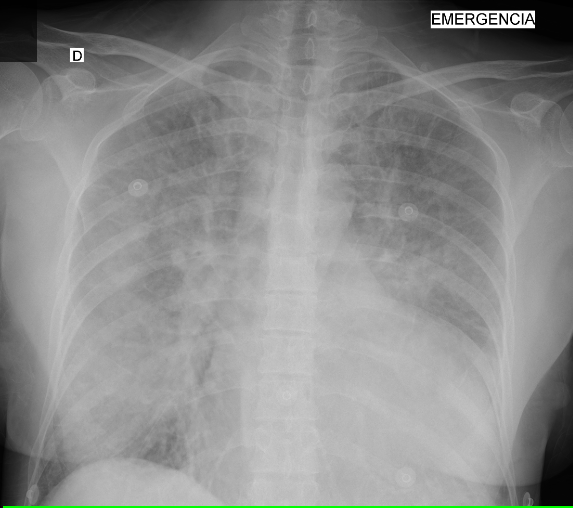

Uma mulher de sessenta anos de idade deu entrada em serviço de emergência com relato de dor torácica retroesternal leve, sem irradiações, com sensação subjetiva de dispneia associada. Previamente com relato de miocardite viral por covid e hipertensão arterial sistêmica, em uso irregular de medicações, ao exame físico da admissão, estava lúcida e orientada, com pressão arterial de 150 x 100 mmHg, bilateralmente, frequência cardíaca de 124 bpm, frequência respiratória de 28 irpm e saturação de 91% em ar ambiente, evoluindo, durante a avaliação, com piora da dispneia, progressivamente, assim como com a ausculta evidenciando estertores até o ápice pulmonar. Realizou, também, a radiografia seguinte.

Com base nesse caso hipotético, assinale a alternativa que apresenta a conduta que deverá ser adotada no momento.